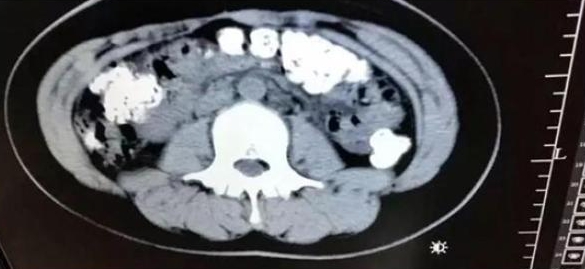

綜合陸媒報導,14歲的小妹妹連續5天沒有排便,不僅沒有胃口,肚子也相當疼痛,由於身體快要承受不住,小妹妹在父母的陪同下到醫院急診。小妹妹一走進診間,醫生就注意到小妹妹肚子鼓鼓的,於是安排腹部電腦斷層掃描,孰料,映入眼簾的畫面讓醫生感到震驚,仔細一看,小妹妹的胃部、橫結腸、升結腸、降結腸、乙狀結腸一直到肛門,都呈現顆粒狀陰影,目測至少超過100顆。

▼小妹妹的胃部一直到肛門,都擠滿未消化的珍珠。(圖/翻攝自浙江24小時)